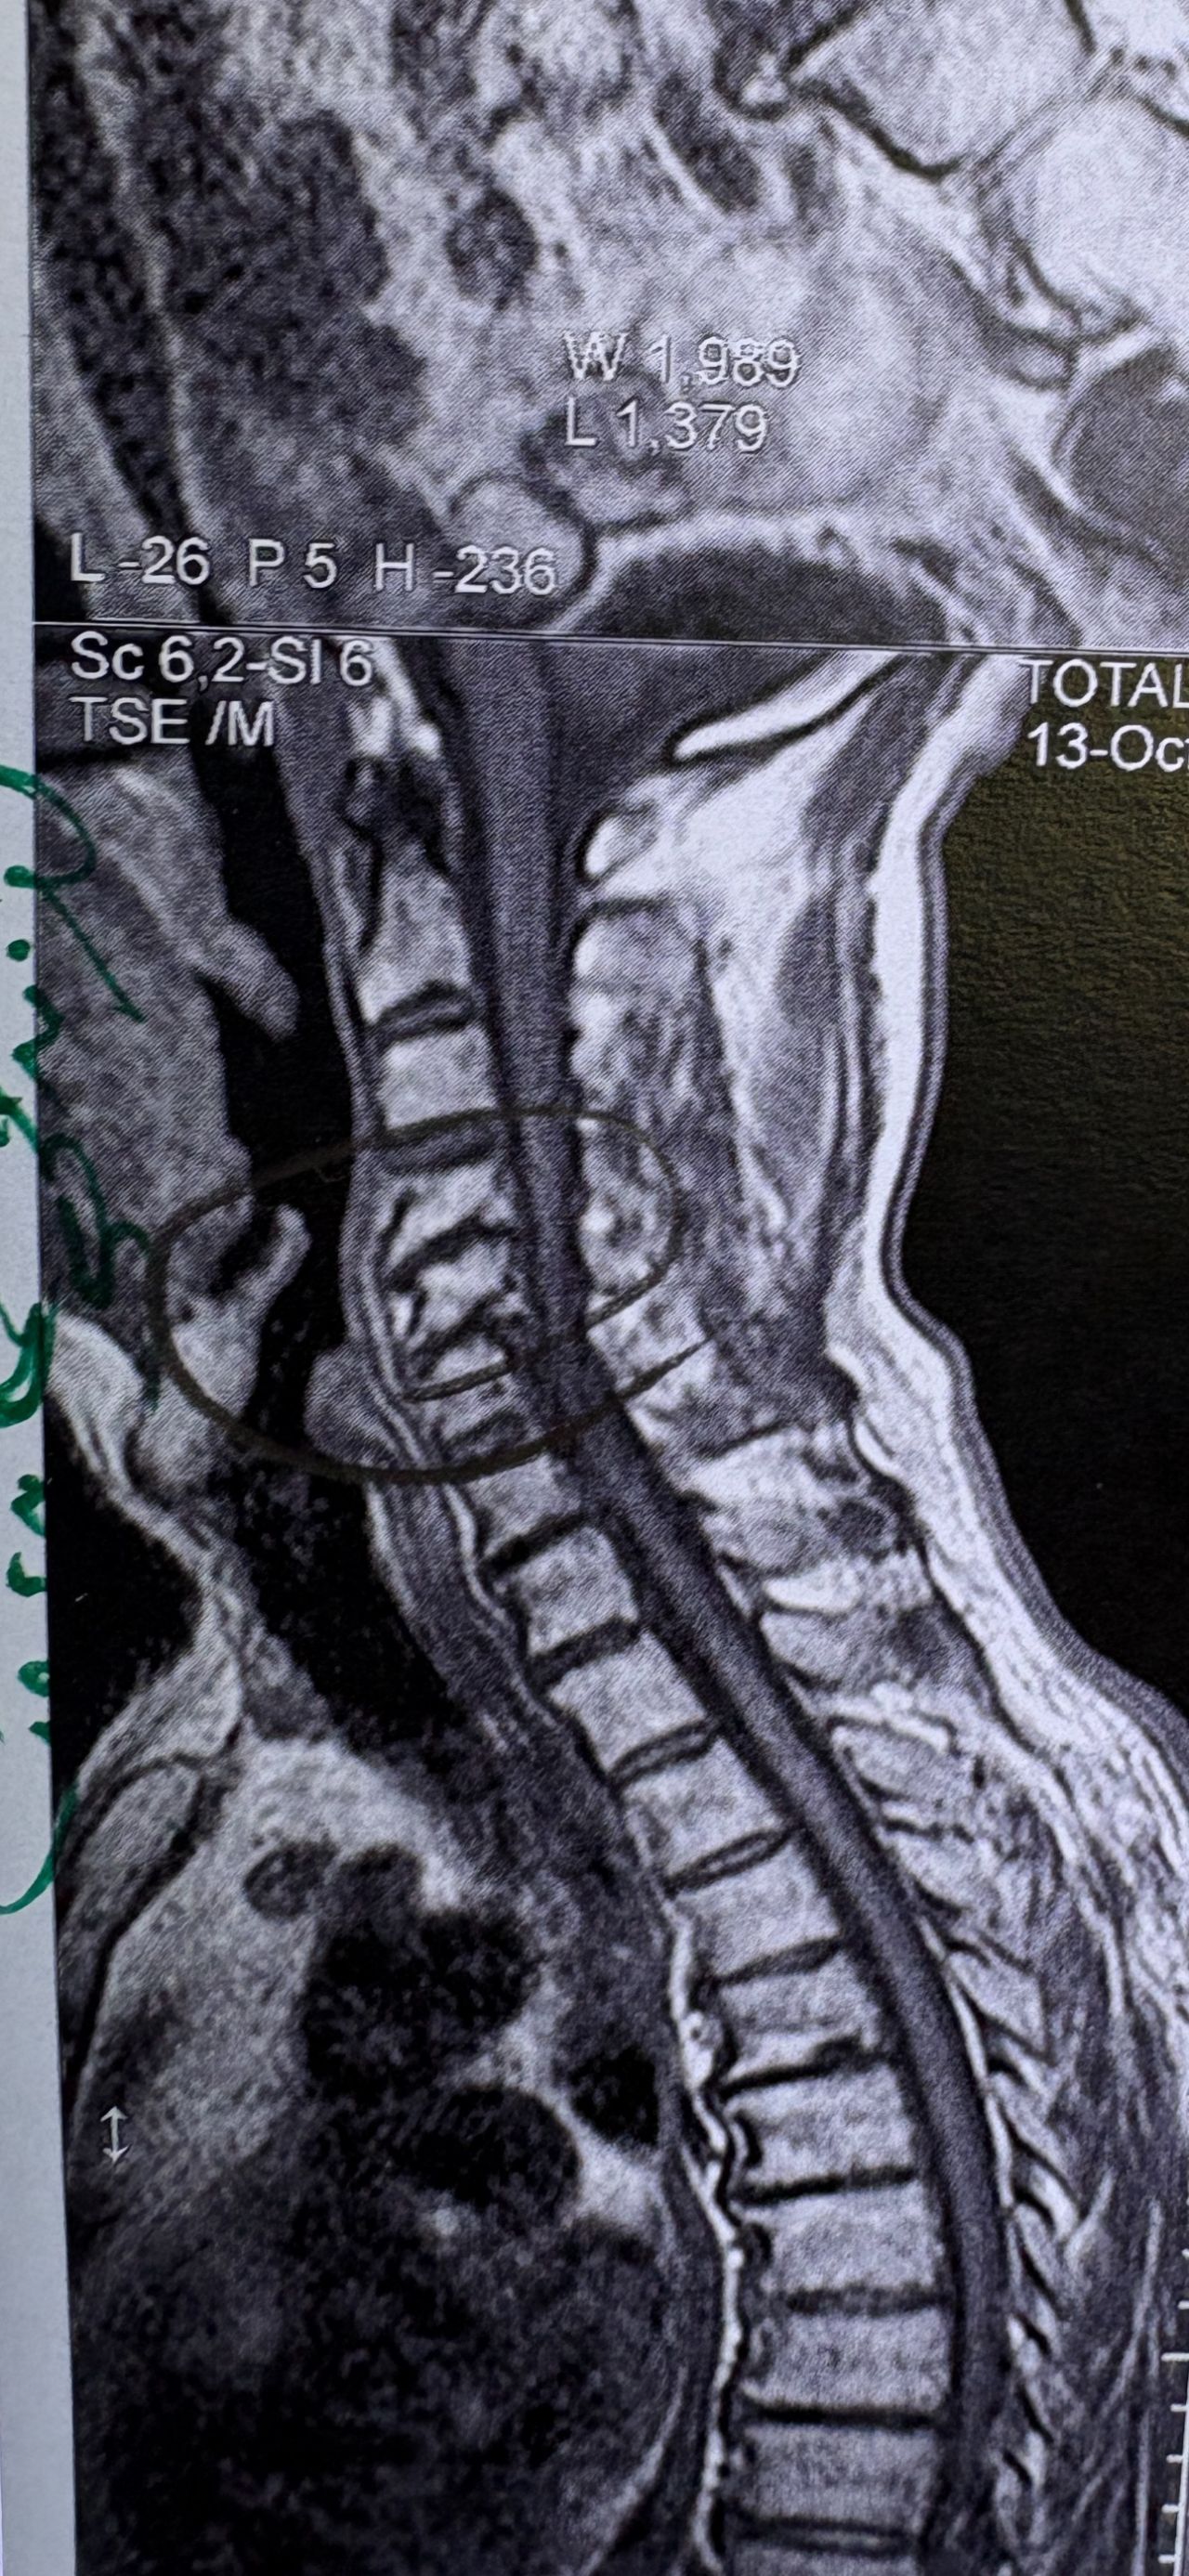

41 years old man presented to my clinic in October 2023 with acute and sever R neck pain with radicular pain to his R upper extremity along C6 dematom since 2 weeks ago. Examination didn’t show any upper motor signs. Was suggested urgent surgery

I ordered EMG/ NCV : showed mild R C6, C7 irritation without any active axonal loss

In his MRI was reported R. para R. IVF Massive extrusion. I decided to control his pain and manage this patient with reevaluation of patient every other session. For 5 sessions i just used acupuncture and laser and IFC and mild adjustments to his R. T3-T7 and mild arthosteem to above and below involved segment. Cervical adjustment considered contraindicated for this patient. From session 6th- 8th i started to use mild/gentle cervical decompression. He used soft cervical collar all the time. His pain decreased by 80 percent

I gave him cervical traction pump to be used 3-5 times per day at home for the next 3 months and i released the patient. He was evaluated every week once for one month and after that every 2 weeks. After 3 month I repeated MRI. Size of the herniated disc was reduced greater than 50 percent. Asked him to do another mri in 6 months

In general: Precise selection of the patients, examination,diagnosis, plan of management, reevaluation and treatment can be done by doctors of chiropractic for the patients with spinal disc herniation and stenosis Moreover giving reasonable time to these kind of patients under direct supervision by their chiropractic doctors can prevent unnecessary surgery. Proper selection of these kind of patients is another important fact that can be done precisely by chiropractors.

MRIs before and after proper management of this patient: